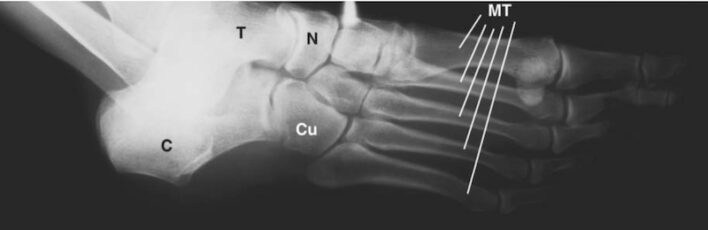

LIÊN HỆ X QUANG

Ghi chú chữ viết tắt:

- C = Calcaneus; Xương gót

- Cu = Cuboid; Xương hộp

- T = Talus; Xương sên

- N = Navicular; Xương ghe

- MT = Metatarsal; xương bàn